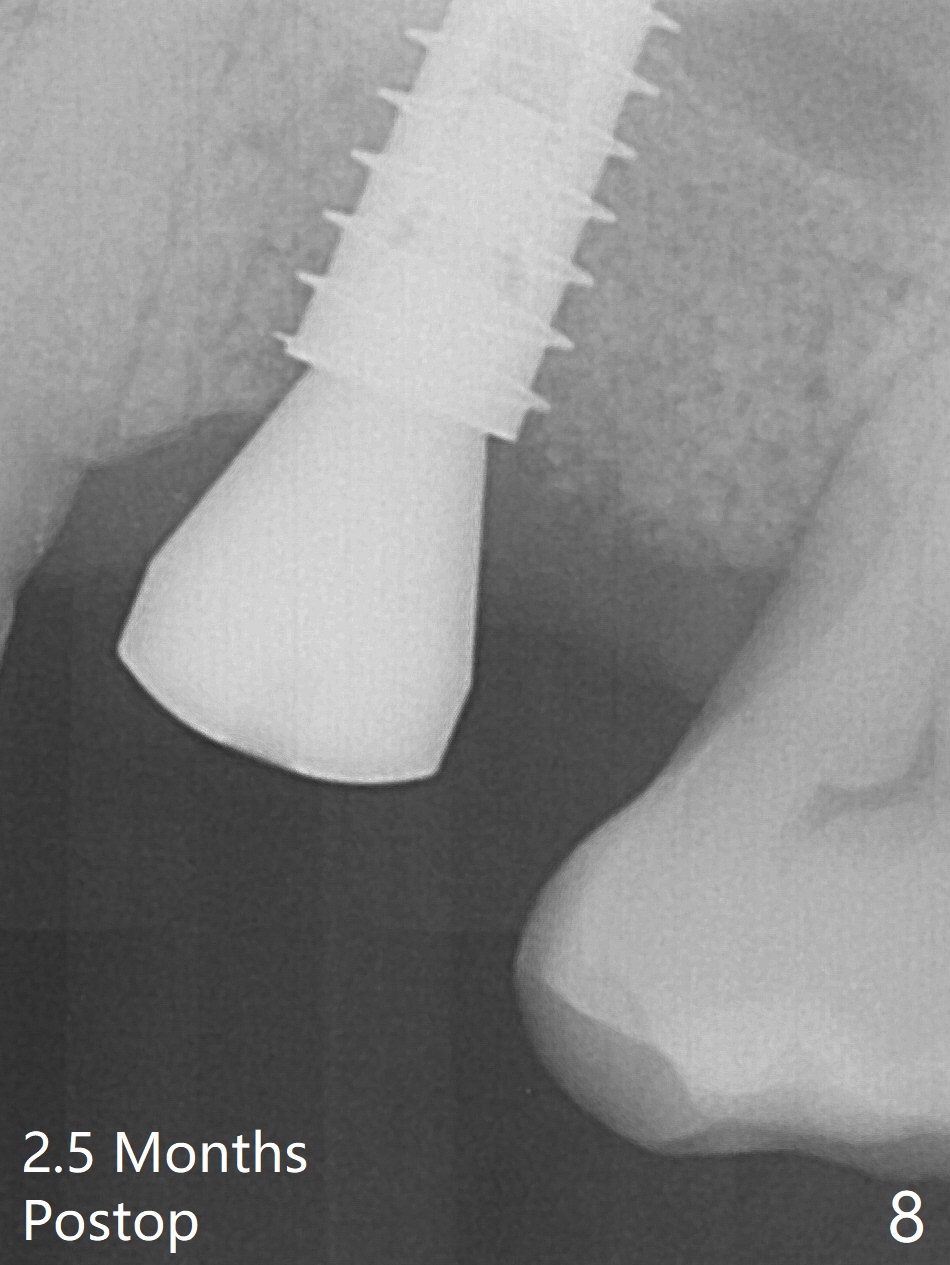

After extraction of the tooth #14 with palatal root fracture (Fig.1 <), sinus membrane perforation is found in the buccal wall of the palatal socket (Fig.2 ^). Osteotomy is initiated in the buccal strut of the septum (Fig.3 *). As the osteotomy increases in diameter, it slides into the mesiobuccal socket (Fig.4). A 5x9 mm implant is placed slightly mesial; after placement of a 6.5x4(2) mm abutment and insertion of collagen plug in the palatal socket, Vera graft is placed in the remaining socket space (Fig.5 *). Nasal hemorrhage persists 1.5 months postop (Fig.6). The distal gingiva is slightly tender and erythematous; a 6x4 mm healing abutment is placed 2.5 months postop (Fig.7,8). Impression is taken after laser gingivectomy 3.5 months postop. The patient feels discomfort at the site 7 days post impression, although the gingiva heals after laser treatment. Two weeks after cementation, the mesial gingiva is mildly tender and the abutment screw is loose. A 6x3 mm healing abutment is placed. The abutment/crown is reseated 10 months postop (Fig.9).